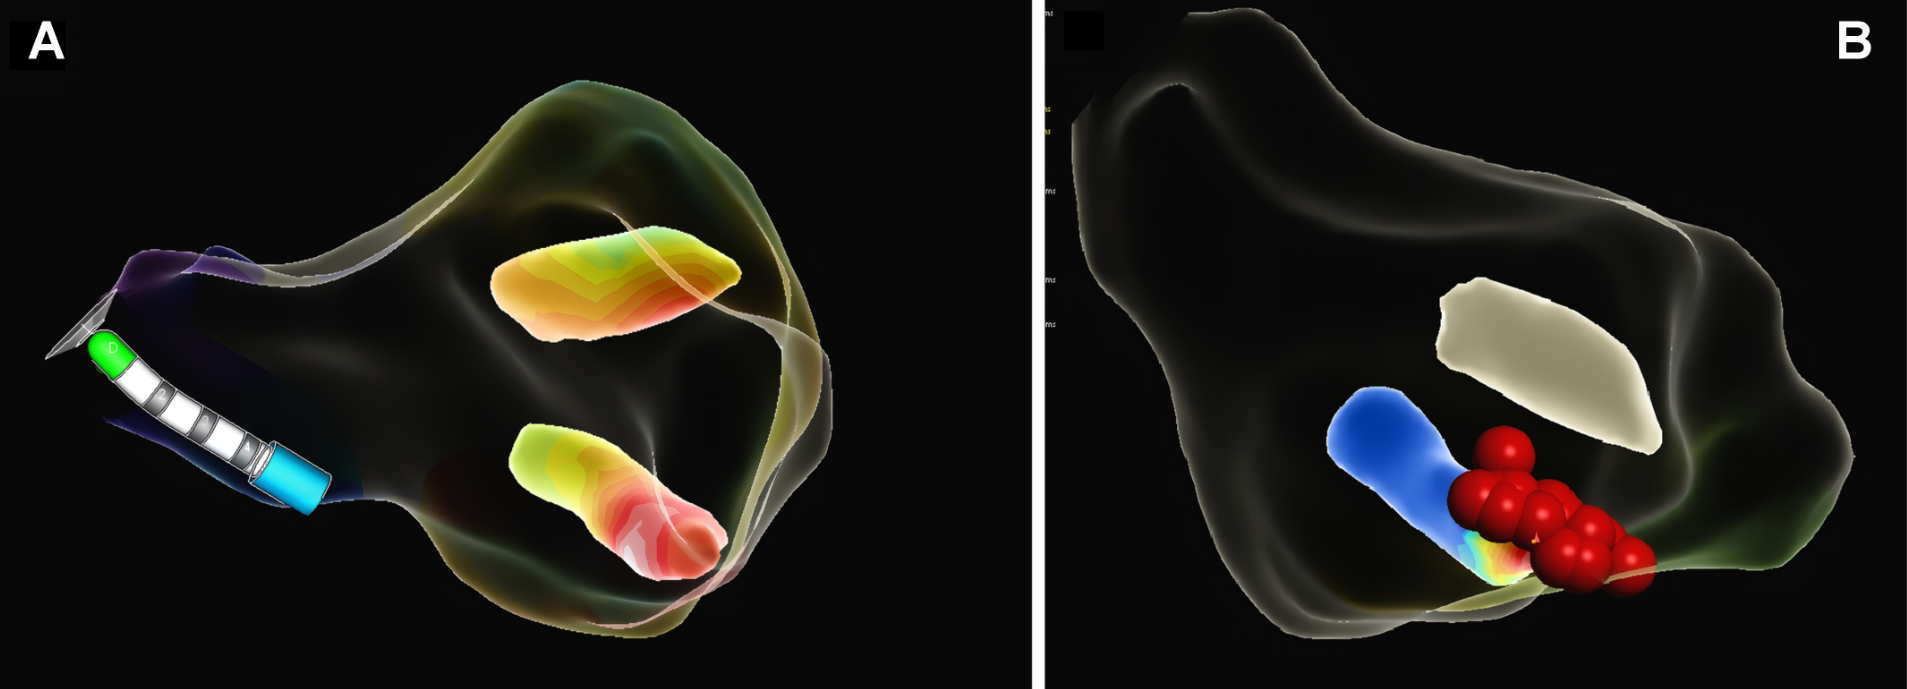

A 68-year-old man with a history of systemic arterial hypertension, under treatment with bisoprolol, with no family history of premature coronary artery disease or sudden cardiac death. The patient consulted for frequent episodes of "palpitations" of long duration. During outpatient follow-up, a cardiovascular stress test was requested, presenting dyspnea, monofocal Premature ventricular contraction and sustained ventricular tachycardia (VT) at maximum effort (Figure 1A). Because VT is a risk marker for sudden death, the patient was hospitalized. During his stay in the emergency department, an electrocardiogram was performed and showed sinus rhythm with T-wave inversion from V2 to V6 (Figure 1B). Transthoracic echocardiography showed left ventricular hypertrophy of apical predominance (Figure 1C), with a polar Strain map showing abnormal longitudinal function in the apical segments (Figure 1D).

Figure 1. (A): Stress test with report of sustained ventricular tachycardia (VT) in maximal stress event with unified ventricular duplets. (B): Electrocardiogram showing sinus rhythm with marked wide-based negative T-wave inversion of V2-V6. (C): Transthoracic echocardiogram short axis view and four chambers with increased thickness at the apical level, also note the "Ace of Spades" shape in the apical segment and the decrease in the interventricular volume. (D): Polar map of global longitudinal myocardial deformation showing involvement of the apical segments with a tendency towards the anterolateral and medial inferolateral segment